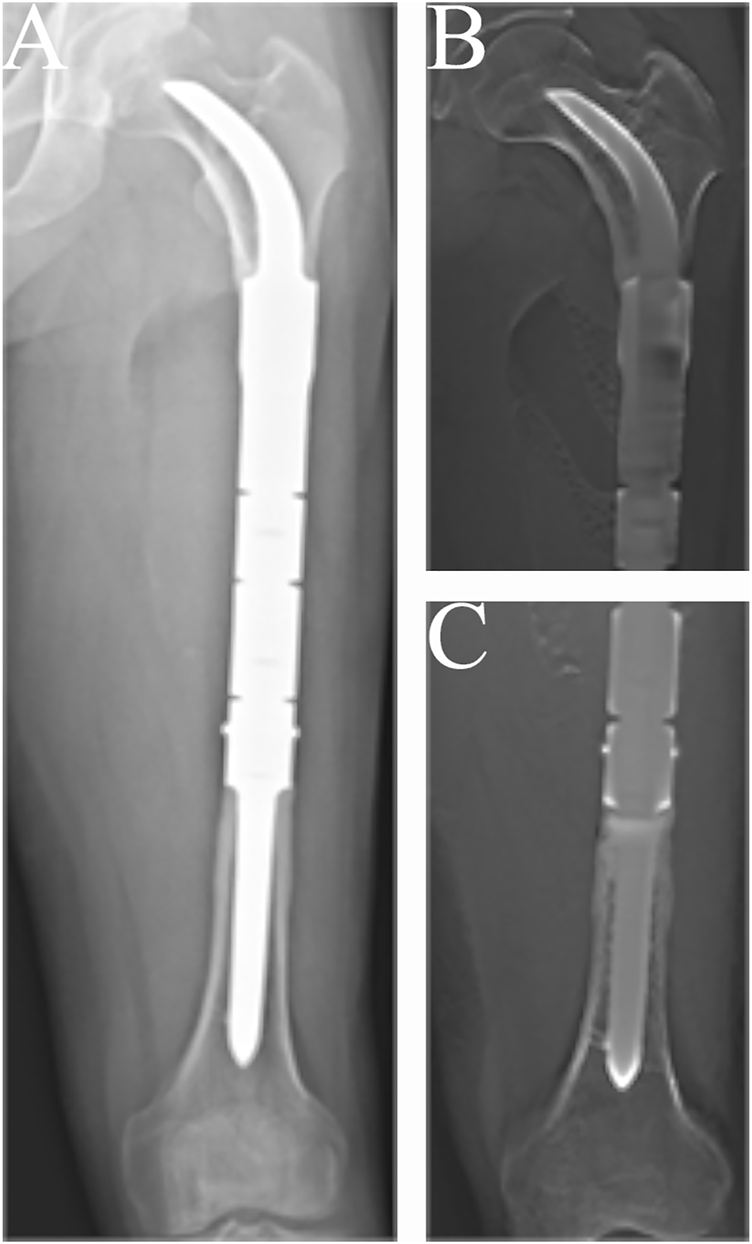

FIGURE 3

Radiographs showing the 57-months postoperative views of the customized cementless intercalary endoprosthesis with an intra-neck curved stem placed during treatment for an osteosarcoma. (A) Posteroanterior radiograph of the entire femur. (B) Posteroanterior tomosynthesis with Shimadzu Metal Artefact Reduction Technology (T-smart) views of the stem insertion region in the proximal femur. (C) Posteroanterior T-smart views of the stem insertion region in the distal femur.

The condition of the bone–prosthesis interface was evaluated by X-ray and T-smart. No fretting wear around the endoprosthetic stem was found in the enrolled patients. We also found no obvious radiolucent line, and radiographic signs of bone ingrowth on the bone–stem interface were found in all stems. A typical case of postoperative neocortex formation is shown in Figure 3. In one patient, the CCIE with an INCS was used in the femoral diaphyseal defect reconstruction after resecting >70% of the femoral length owing to massive tumor resection, and a stable bone–prothesis interface was achieved at the last follow-up (Figure 4). Compared with the distance from the center of the femoral head to the midline of the body and the apex of the acetabulum preoperatively, the distance from the tip of the INCS to the midline of the body (p = 0.187) and the apex of the acetabulum (p = 0.159) was not statistically significant postoperatively. Furthermore, the femoral neck–shaft angle did not differ significantly between pre- and postoperative values (p = 0.793) (Table 2). Thus, the INCS positions were deemed accurate.

In our study, no obvious radiolucent lines between the implant and the bone were found on the proximal femur on mediolateral or anteroposterior X-ray views. Moreover, bone ingrowth on the bone–stem interface was found for all stems. In addition, compared with previous studies (Calvert et al., 2014; Dieckmann et al., 2014) of reconstructing femoral diaphyseal defects with a UPF, the rate of aseptic loosening in our study was low. We believe the reasons are as follows: (1) The endoprosthesis we used to reconstruct femoral diaphyseal defects with a UPF was a good fit with the anatomy of the proximal femur, and the INCS positions were deemed accurate postoperatively. (2) The INCS reduces the offset distance between the long axis of the femur and a line passing through the center of the femoral head and condyles, which is considered a measure of the bending moment about a dorsoventral axis at any level (Unwin et al., 1996). Compared with a straight stem, the offset distance of an INCS is smaller; therefore, the bending moment is also smaller, which may be an important factor in decreasing the rate of aseptic loosening of the endoprosthesis (Wyatt et al., 2019). (3) The INCS is coated with hydroxyapatite or 3D-printed porous titanium, which can facilitate biological bone ingrowth at the bone–prosthesis interface (Van der Stok et al., 2013; Lu et al., 2018; Zhao et al., 2020). (4) The curved stem we used has two fins, symmetrically arranged in the medial and lateral planes at the base of the stem, providing guidance for implantation and an additional derotational force (Figure 4C).